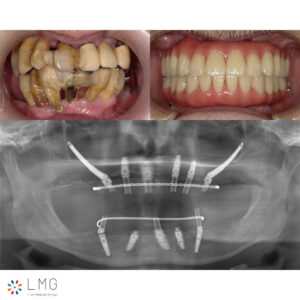

ザイゴマインプラント治療 「ザイゴマインプラント治療」を行われた患者さまのビフォーアフターをご紹介します。 ※ご紹介している症例は、あくまでも患者様固有の症例ですので、実際には患者様によって治療期間や、治療法など個人差が […]